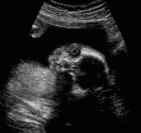

Yandaki ultrasonda bebeğin yüzü ve göz boşluğunun içinde lens

(mercek) yapısı görülmektedir.